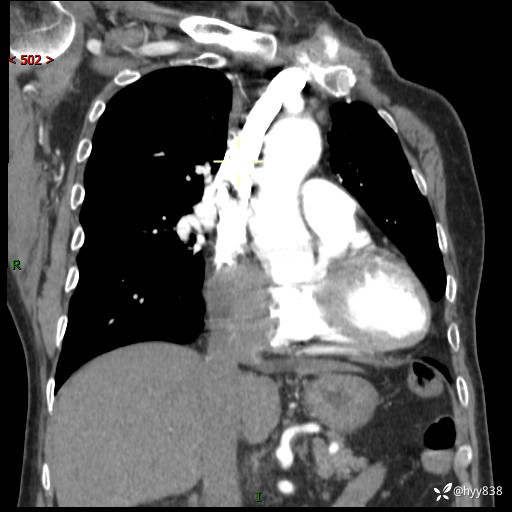

老年男性,检查发现心脏肿物1周余。少见病例,请讨论---结果公布~

主诉:检查发现心脏肿物1周余。

现病史:患者一周余前因腹胀就诊我院消化科门诊,查心脏彩超提示右房内异常回声(粘液瘤?),无明显心慌、气喘、胸闷,无明显胸痛、咳嗽咳痰等不适,活动量增加后出现心慌、气喘不适。现为求进一步治疗,就诊我科,门诊遂以“心脏肿物”收入院。 自发病以来,精神睡眠一般,食欲尚可,大小便正常,体力下降,体重无明显变化。

胸部CT平扫+增强